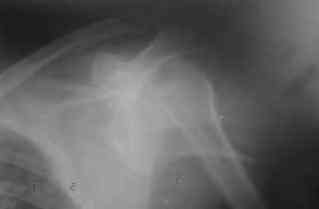

Dear all, A heavy built 30-year-old male patient sustained fracture dislocation of left shoulder about 8 months back.

For this ORIF with K-wires was done elsewhere. K-wires were removed at 6 weeks and patient advised physiotherapy. He has been doing physio dedicatedly since then.

He has 60* elevation…primarily it is scapulothoracic motion. External rotation at side is minus 30*.

Movements are painful.

Looking at his previous x-rays, I was thinking of refixing the greater tuberosity, however got an axillary view done today which was never done during this period and this shows non-union.